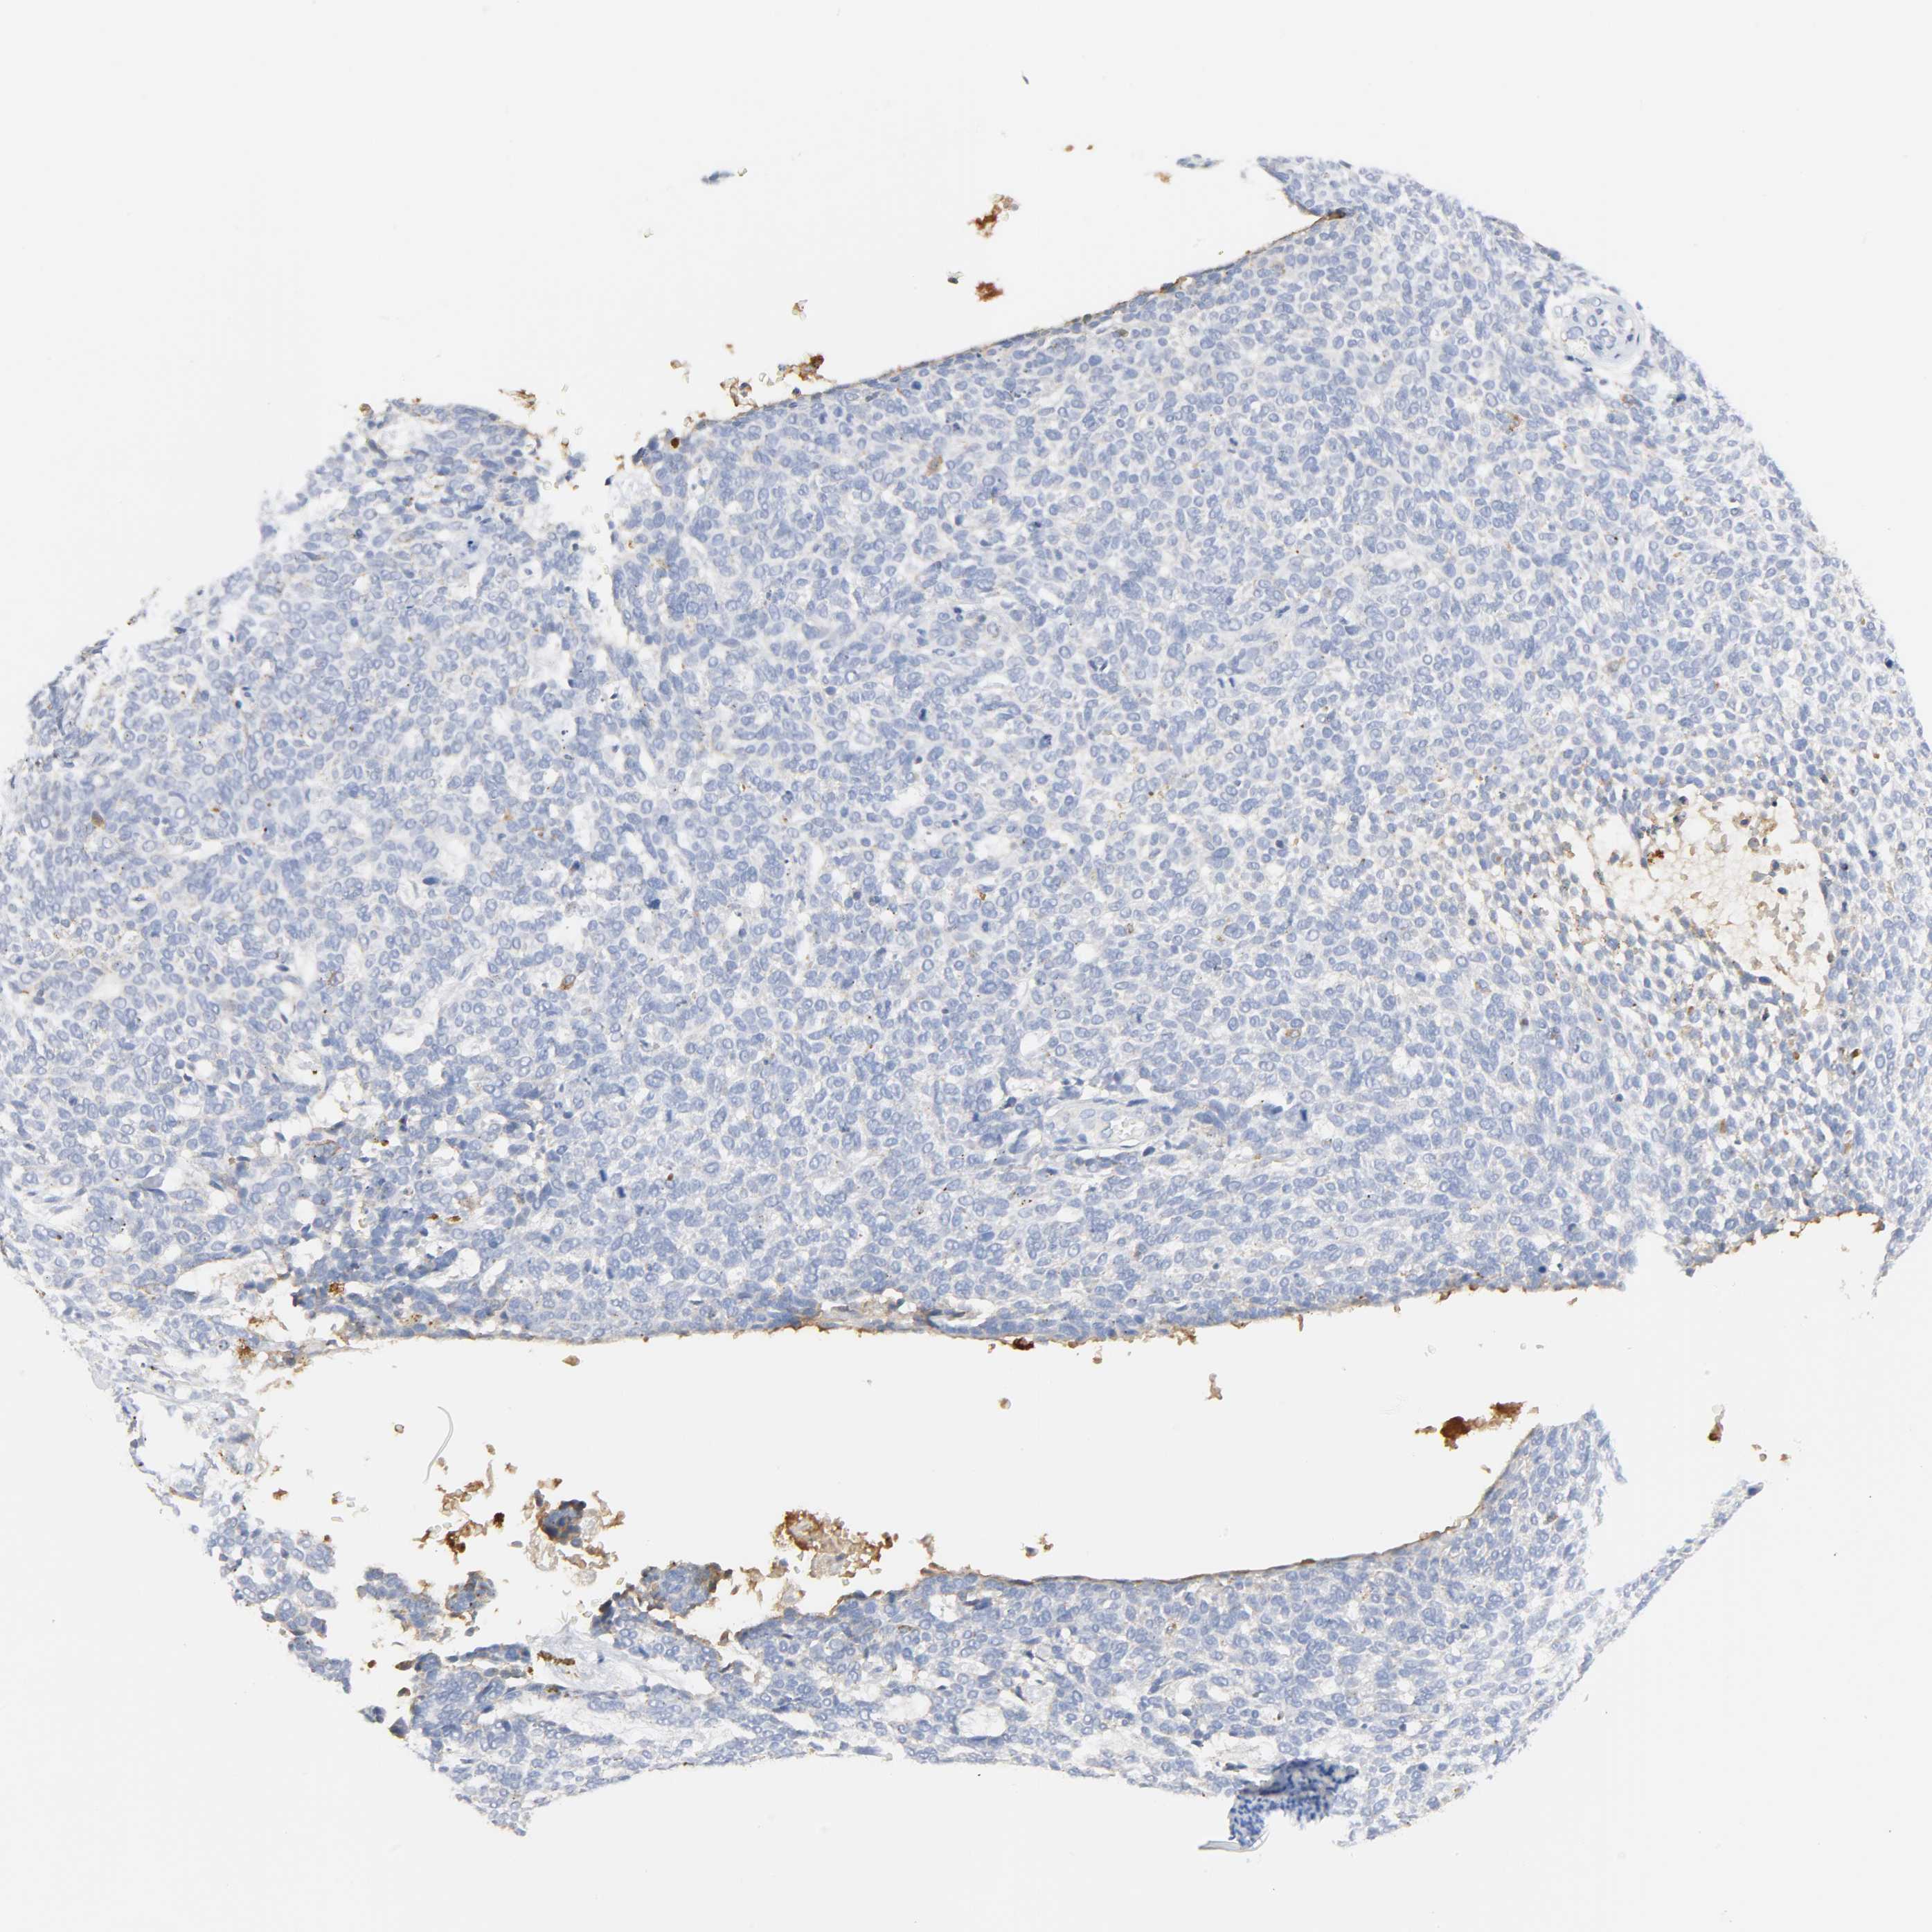

SKIN CANCER - Protein expressioni

A mouse-over function shows sample information and annotation data. Click on an image to view it in a full screen mode. Samples can be filtered based on level of antibody staining by selecting one or several of the following categories: high, medium, low and not detected. The assay and annotation is described here.

Antibody stainingi

Antibody staining in the annotated cell types in the current human tissue is reported as not detected, low, medium, or high, based on conventional immunohistochemistry profiling in selected tissues. This score is based on the combination of the staining intensity and fraction of stained cells.

Each image is clickable and will lead to virtual microscopy that enables deeper exploration of all samples and also displays staining intensity scores, fraction scores and subcellular localization as well as patient and tissue information for each sample.

Antibody HPA003756

Staining

High

Medium

Low

Not detected

Intensity

Strong

Moderate

Weak

Negative

Quantity

>75%

75%-25%

<25%

None

Location

Nuclear

Cytoplasmic/membranous

Cytoplasmic/membranous,nuclear

Squamous cell carcinoma, NOS

Basal cell carcinoma